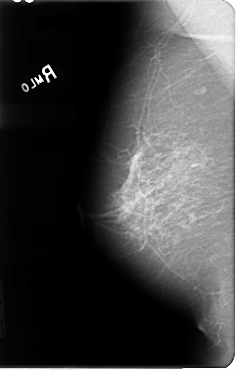

B_3046_1.RIGHT_MLO

RIGHT_CC LINES 4792 PIXELS_PER_LINE 3056 BITS_PER_PIXEL 12 RESOLUTION 50 NON_OVERLAY

RIGHT_MLO LINES 4800 PIXELS_PER_LINE 3072 BITS_PER_PIXEL 12 RESOLUTION 50 NON_OVERLAY